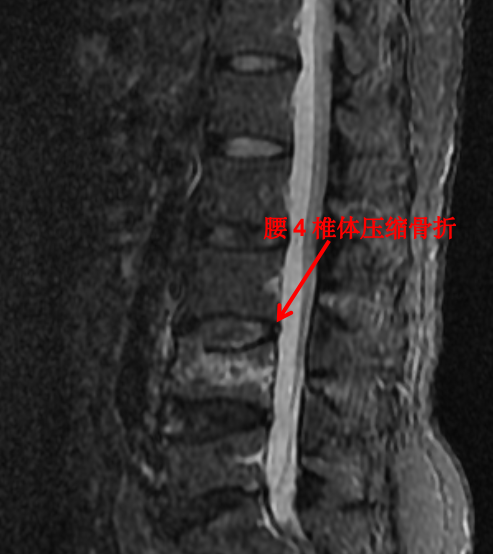

隨著科技進(jìn)步及醫(yī)學(xué)的發(fā)展,核磁已經(jīng)是脊柱外科不可或缺的檢查手段。對(duì)脊柱、韌帶、椎間盤(pán)、椎管內(nèi)神經(jīng)及椎旁組織顯影都優(yōu)于 CT,通過(guò)腰椎核磁我們可以直觀地看到椎間盤(pán)突出的程度、神經(jīng)受壓的程度,以及壓縮骨折的新鮮程度。

這對(duì)于脊柱疾病的治療有著很重要的指導(dǎo)作用。優(yōu)點(diǎn)是對(duì)脊柱及周?chē)M織顯影更清楚,無(wú)輻射。其缺點(diǎn)是價(jià)格昂貴,檢查時(shí)間長(zhǎng),有幽閉恐懼癥的患者難以接受。

前面提到的腰椎壓縮骨折,X 光片可以看出楔形變,但無(wú)法判斷新鮮骨折還是陳舊骨折,進(jìn)一步完善腰椎 MRI 才能明確診斷,做出下一步治療計(jì)劃。